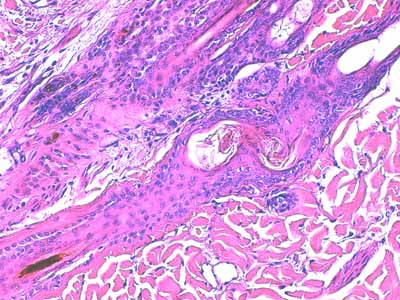

Biopsies cutanées

Sur l’une des biopsies, l’épiderme et les structures annexielles sont nécrosées ainsi que de larges plages de fibres de collagène dans le derme profond (Fig6). Dans le derme périannexiel, on observe une discrète hypercellularité diffuse sous la forme de cellules pycnotiques (Fig2,3,13,14). En profondeur, dans l’hypoderme, on observe une dilacération des septa conjonctifs interlobulaires et des adipocytes par un matériel sérofibrineux, parsemé d’une poussière nucléaire entourant parfois des structures vasculaires, artériolaires et veineuses, de moyen calibre dont la lumière est occupée par un thrombi fibrineux et dont les cellules endothéliales apparaissent vacuolisées (Fig7,8,9). Sur les autres biopsies, l’épiderme montre des lésions de dégénérescence réticulaire (Fig3,4,5). Cet aspect est associé à un décollement épidermique multifocal(Fig2,3). Le derme superficiel est œdémateux (Fig3,4,5). Au sein des unités annexielles, on observe plusieurs follicules pileux dont la gaine épithéliale folliculaire externe, est plissée sur toute sa longueur. La tige pilaire présente dans le canal pilaire est elle-même circonvolutée, fracturée, la cuticule effritée (Fig2,10,11,12) . Le cycle folliculaire est normal, la phase anagène prédomine. Autour des structures annexielles, on observe de petits foyers de taille variable, nécrotiques, avec une poussière cellulaire et probablement un matériel fibrinoïde (Fig13,15). On perçoit encore la silhouette de certaines structures vasculaires dont la lumière semble obstruée de thrombi. On en retrouve, dans les septa conjonctifs interalvéolaires, des lobules adipeux. A noter, que sur l’une des biopsies, se trouvent incluses dans le tissu adipeux, des tiges pilaires tortueuses. Dans plusieurs territoires dermiques nécrotiques, on observe, au fort grossissement à l’objectif à immersion, des silhouettes vasculaires tapissées de reliquats de cellules endothéliales, au cytoplasme vacuolisé avec chromatolyse nucléaire. En périphérie, les fibres de collagène prennent un aspect coagulé, basophile. Elles montrent une multitude d’éléments bacillaires associés à des dépôts acidophiles, probablement fibrinoïdes (Fig16).

Photo 16 (Hémalun-Eosine X1000, objectif à immersion) : vue rapprochée au fort

grossissement, d’une plage cellulaire inflammatoire dermique en étroit rapport avec

un follicule pileux : le matériel basophile semble contenir des silhouettes en bâtonnets,

compatibles avec des bacilles bactériens.

Légendes de la Photo 16 :

- Étoiles rouges pleines : trousseaux de fibres de collagène

- Flèches turquoises : silhouettes en bâtonnets suggérant des bacilles bactériens libres dans le derme et formant le matériel granuleux des plages cellulaires inflammatoires

- Double flèche verte : derme